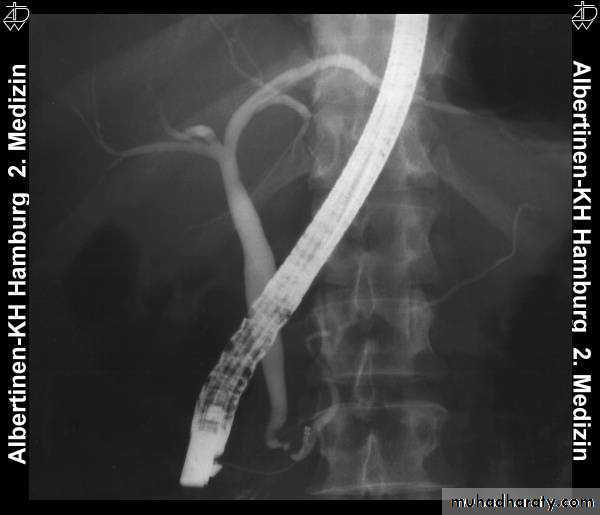

ERCPDxtic

TherapeuticCx

PTC

Obstructive jaundice

US

CT

ERCP & MRCP